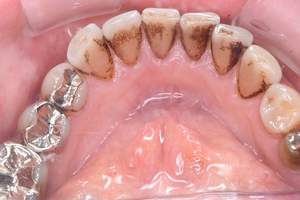

治療前 1

治療後 1

治療前 2

治療後 2

治療前 3

治療後 3

| 年齢 | 58歳・女性 |

|---|---|

| 主訴 | 前歯の着色除去希望 |

| 治療内容 | エアフロー |

| 費用 | 合計:5,500円 (2024年8月現在) |

| 治療期間 | 60分 |

| リスク・副作用 | 呼吸器疾患のある方や放射線治療を行っている方、ナトリウム摂取制限を必要とする方や妊娠中の方は処置を受けられないことがあります。 施術を受ける際、舌や歯肉に当たった粒子でチクチクとした痛みを感じることがあります。 |

| 治療方針 | 歯周病と虫歯の治療を担当医と相談し進めていく予定です。 |

| 担当者所見 | 約4年ぶりの来院でした。他の歯医者に行っても満足いくクリーニングをしてもらえず悩んでいる様子でした。問診時には手で口元を隠すようにお話されていましたが、エアフロー後は笑顔でお話するようになっていました。 |